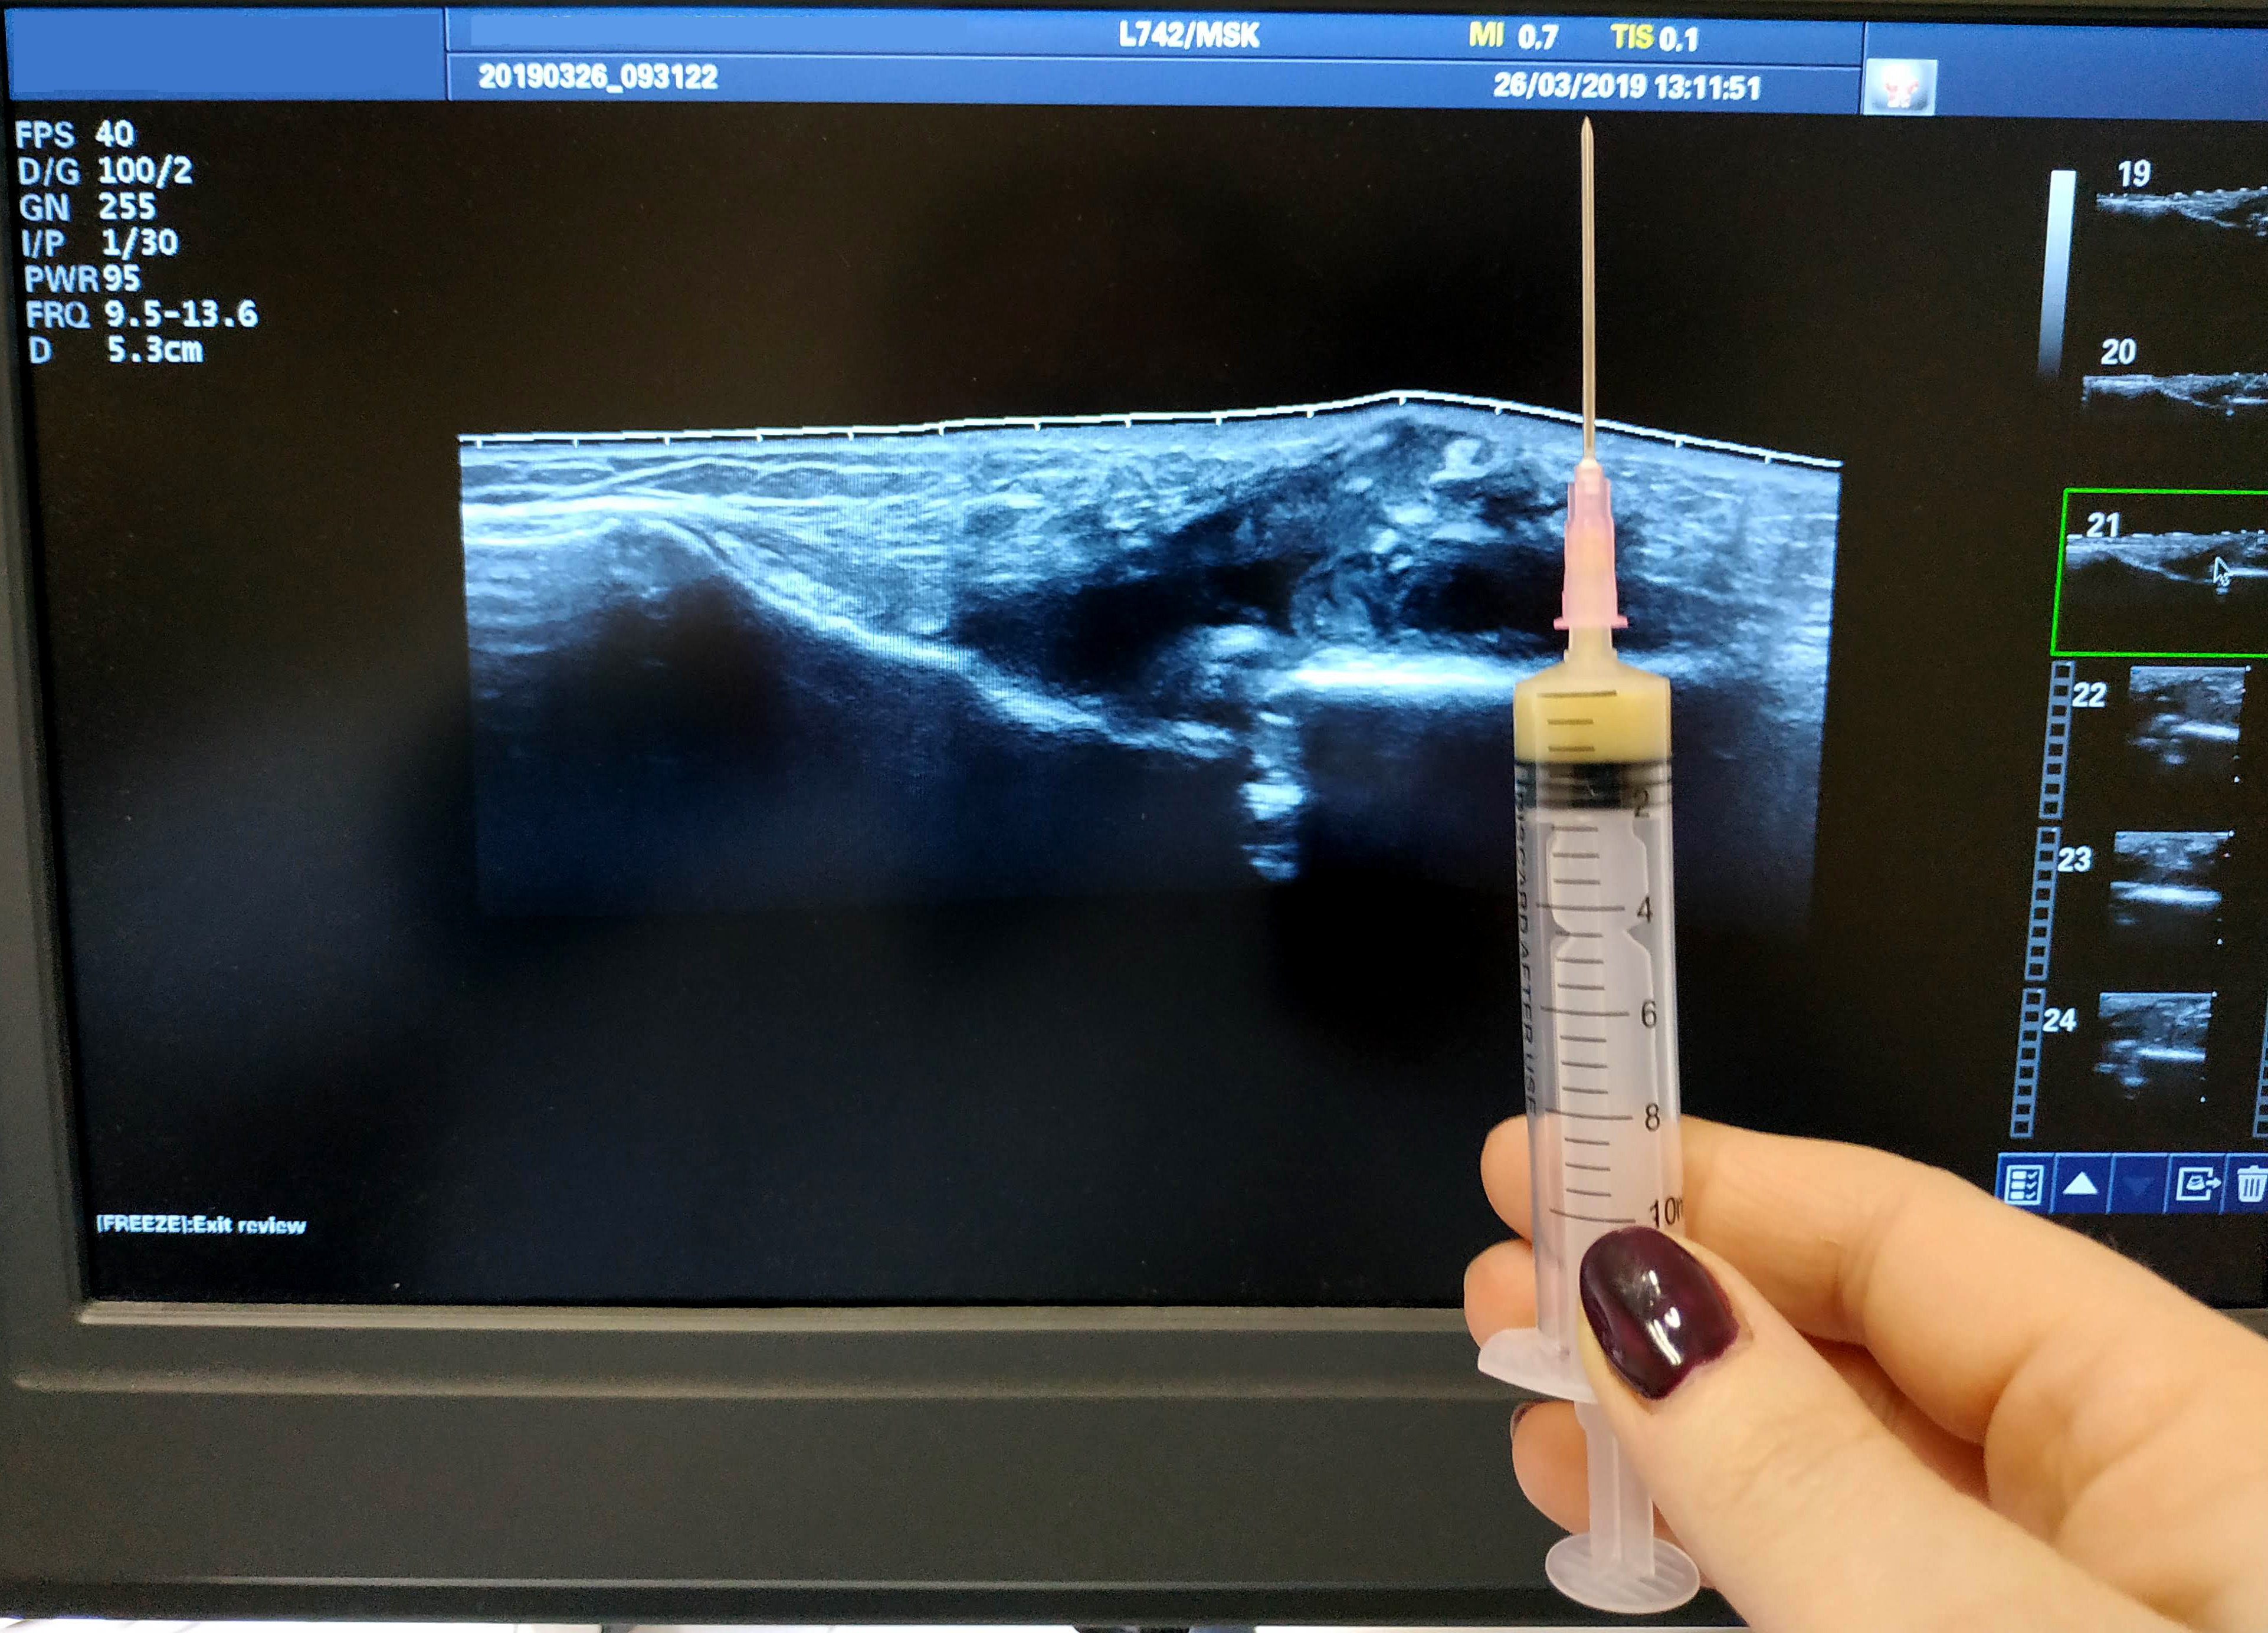

Пункция под контролем УЗИ

IMG_20190326_12163311.jpg